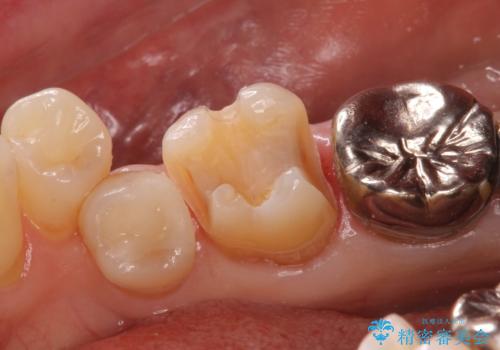

白くて適合の良い詰め物が入ったことで大変喜んでいただけました。

奥の銀歯も今後やり変えていきたいとのご希望もいただきました。